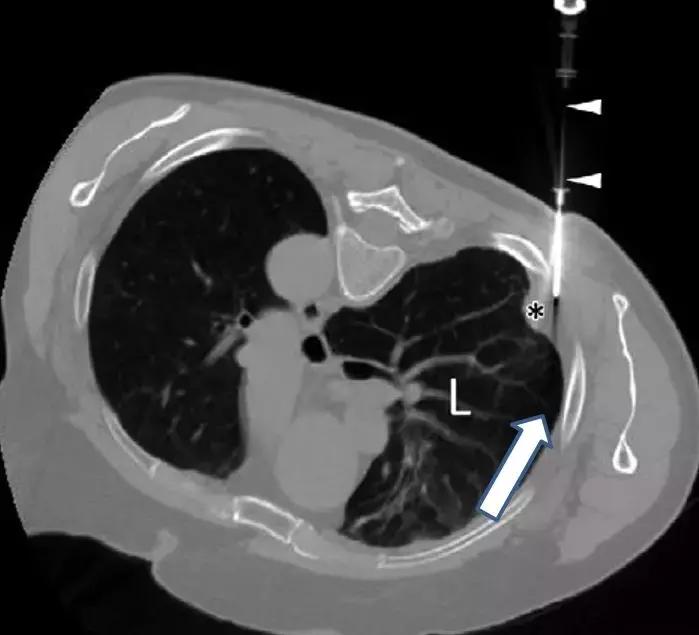

三、彩超引导下胸膜活检

超声指引下,切割活检针达到目标部位后扣动弹簧扳机完成活检,所以特异性和敏感性都不错。

文献报道,CT或超声引导下的胸膜活检对胸膜恶性疾病诊断的敏感性达70~91%,而盲穿胸膜活检对胸膜恶性疾病的敏感性仅为40~75%。

在有条件的医院,应鼓励开展影像引导下的胸膜活检以提高对胸膜疾病的诊断率和安全性,尤其是针对局灶性胸膜病变者。

这是在彩超引导下的胸膜活检,胸水较少,胸膜局灶增厚。在穿刺中,可以看到针的所在位置。

优点:实时引导、无射线暴露、费用相对较低。

缺点:依赖超声仪器品质,因为不同的机器达到的效果不同;另外,由于超声扫描的Total的放置角度、位置都对成像有影响,所以超声医师的经验也很重要。